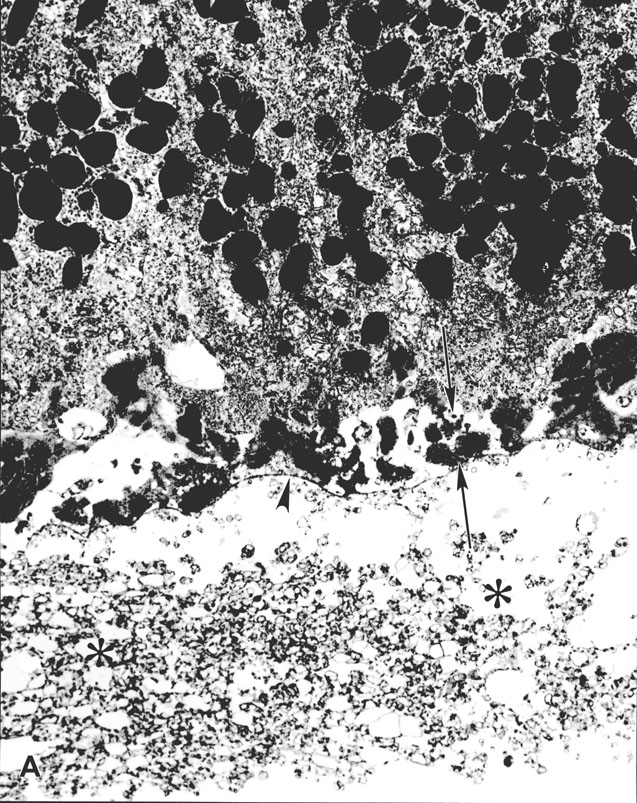

Figure 3. Basal linear deposit

A. Ultrastructural appearance of a 6.4 µm-thick basal linear deposit composed of vesicular material (asterisks) located between the retinal pigment epithelial basal lamina (arrowhead) and the remainder of Bruch's membrane. A 2.2 µm-thick layer of wide-spaced collagen (basal laminar deposit, between arrows) is present internal to the retinal pigment epithelial basal lamina (arrowhead). x15,000.

Figure 3A reprinted with permission, from: Green WR, Enger C. Age-related macular degeneration histopathologic studies. The 1992 Lorenz E. Zimmerman Lecture. Ophthalmology 1993; 100:1519-35.